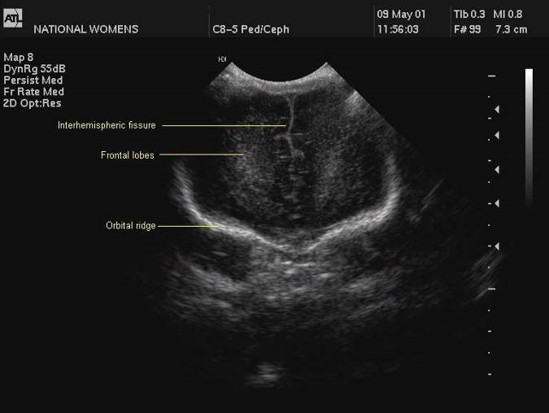

Measurement of the ventricular system needs to be performed on a symmetrical, easily reproducible view. The ventriculo-cranial ratio (VCR) is the ratio of distance between the lateral sides of the ventricles and the biparietal diameter. This is usually expressed as a percentage with a normal value of around 33-36% in a preterm infant. This value is of most use in monitoring the degree of change between successive measurements. An increasing VCR should trigger frequent reassessments with measurements of the cerebral resistive index (see below).